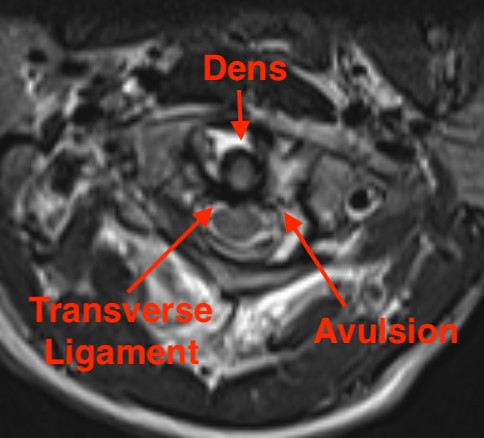

MRI

Assess ligamentous injury, specifically transverse ligament

Dickman et al Neurosurgery 1996

- type I:  intra-substance TAL tears

- type II:  fractures or avulsions of the TAL from the tubercle of the lateral mass of the atlas

MRI demonstrating intra-ligamentous injury (blue arrow)

Jefferson MRI 1Jefferson MRI 2

MRI demonstrating avulsion of the TAL on the left side